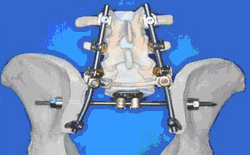

11月の入院は、かあさんに大きな効果がありました。腰部神経根と腹部内蔵神経にブロックを施術して戴いたのです。先生方の今年春以来の懸命な、ご尽力により場所というか、かあさんのお腹の中を熟知してくださった故でしょうか、腰部ではビリッときたようです。それよりも担当の先生から「2月の本当に難しい仙骨摘出をして、これから先ズッと病院生活にならへんやろか。退院できるんやろか」と心配していたんですよ」と聞かされ、又「今の状況は素晴らしい、精神的にも身体的にも回復ですよ」のお話で、「痛みは一緒や、ちっともようなってない」とばかり思い考えていたかあさんが、どうやら変わって退院してきました。 金沢大学医学部整形学科のウェブサイトから、こんな記述と写真を見つけました。この手術もまた金沢大学整形外科で考案した手術方法です。仙骨にできた腫瘍を一塊として摘出する手術方法です。仙骨にできた悪性腫瘍(脊索腫、骨巨細胞腫、転移性腫瘍など)が適応になります。仙骨は脊椎の一番下に存在し、骨盤をつないでおり、脊椎の礎となるところです。そのため仙骨摘出後の再建が大きな問題となりますが、これに関しても金沢大学工学部と共同で研究を重ねて独自の再建法を考案しました。 かあさんは、何とか歩ける機能は温存しておきたいという一念から仙骨の上部は残して、脊索腫が認められる、上縁で切除をしたんだから、大きな神経を切り大切な排泄機能をなくしてでも、歩きたいと考えたのだから、これからも生きている限り痛みと妥協して、好きな時に好きなことをして、痛みを忘れる時間を作りながら、頑張っていこうよ。周囲の里のすべての人たちが、かあさんが、笑顔と大きな声でみんなの輪のなかへ戻ってくる日を待っていてくれるんだから。 もう一つの変化は複合病棟だったので、同室に上顎ガンで手術後、放射線治療中の60歳台の女性と、40歳台の舌ガンの女性から「ガンと闘う強さと明るさ」のパワーをもらって退院してきたのです。家の東西南北、こんな紅葉に包まれた日に、ニッコリ笑って元気になって退院です。そして、昨年11月27日に細胞診の為、2回目の背中の手術をしてから1年グラウンドゴルフを1ラウンド仲間の皆さんの励ましといたわりの中でゲームに参加しました。スコアは21、まだまだ力はありました。カラオケの新曲にも挑んでいます。痛みは無くなりはしませんが、忘れる時間が少しでも長くなれば、奇跡がおこるんではとやがて山里には、厳しい冬が訪れます。訪問看護師さんと笑いながら、話をする声が聞こえます。里の冬は寒さが厳しいのですが、この里には人の温もりがいつもあります。